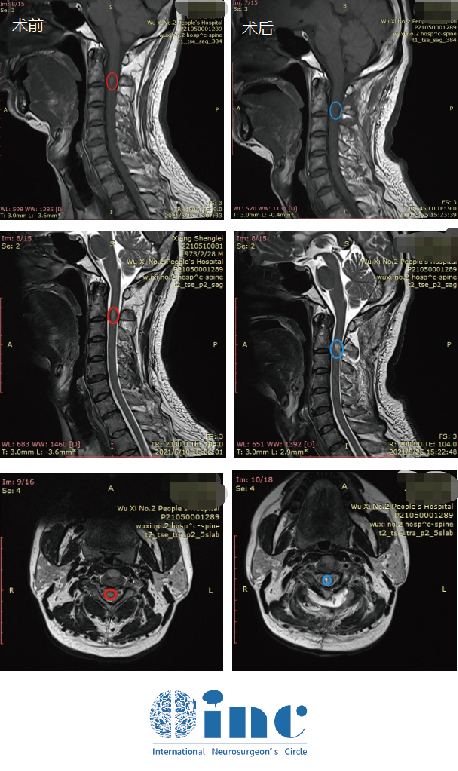

術(shù)前頸2平面脊髓內(nèi)可見(jiàn)橢圓形短T1長(zhǎng)T2信號(hào),信號(hào)較均勻,邊界尚清,大小約7.8X4.1X5.0mm,增強(qiáng)后明顯強(qiáng)化。術(shù)后腫瘤得到順利全切,無(wú)新發(fā)神經(jīng)損傷,無(wú)癱瘓,術(shù)后復(fù)查沒(méi)有復(fù)發(fā)

劉先生的術(shù)前術(shù)后MRI對(duì)比

術(shù)后3個(gè)月回訪:

“8月22日的核磁共振成像看起來(lái)很棒,令人滿意!腫瘤被很好地切除了。磁共振成像上只有一個(gè)很小的切除腔。此外,病理學(xué)方面,我們預(yù)估的室管膜瘤II級(jí)得到證實(shí)。我建議患者未來(lái)每年進(jìn)行一次MRI檢查……”這是INC國(guó)際神經(jīng)外科顧問(wèn)團(tuán)的德國(guó)Helmut Bertalanffy(巴特朗菲)教授對(duì)劉先生術(shù)后3個(gè)月的隨訪回復(fù)。